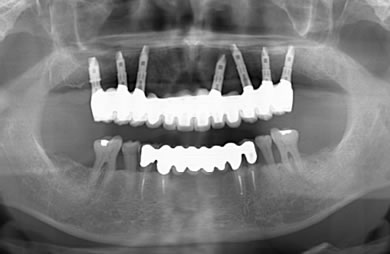

インプラントの症例写真 IMPLANT

骨再生スピードインプラント治療+AGC連結セラミック治療+セラミック治療

| 治療方針 | ソケットリフト法により上顎洞底部を拳上することにより、骨の無い部分に骨をつくってあげ、インプラント治療を可能にする。さらに歯周病により組織の破壊が著しいので、AGC連結セラミック治療により上顎の審美的回復を行う。 | ||||||||||||||||||||||||||||||||

| 治療内容 | インプラント7本(抜歯AGC即日スピードインプラント+ソケットリフト)、AGCハイブリッドセラミック連結ブリッジ1装置(上顎)ハイブリッドセラミック8本 | ||||||||||||||||||||||||||||||||